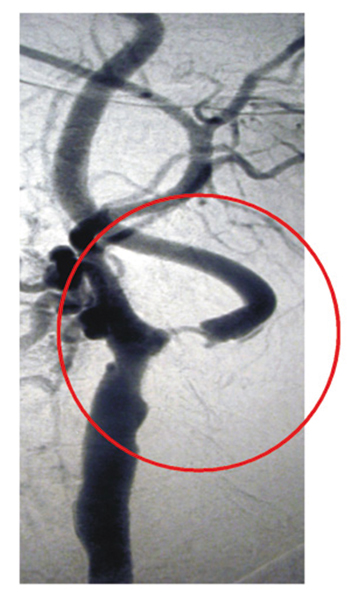

Unter einer Angiografie versteht man eine Gefäßdarstellung, mit der die Durchblutungssituation der Netzhaut beurteilt werden kann. Dies ist unter anderem wichtig bei altersabhängiger Makuladegeneration, diabetischen Netzhautveränderungen oder Durchblutungsstörungen z.B. aufgrund einer Thrombose, oder auch Tumoren.

Um die Gefäßdarstellung durchführen zu können, wird ein gelber Farbstoff in die Armvene injiziert. Anschließend werden mit einer speziellen Fotokamera Bilder von den Blutgefäßen am Augenhintergrund angefertigt. Aufgrund des in die Blutbahn gelangten Farbstoffes können die Gefäße, Gefäßverschlüsse, Gefäßneubildungen (Neovaskularisationen) und auch durchlässige Bereiche (Leckagen) gut dargestellt werden. Die fotografischen Aufnahmen ermöglichen eine genaue Darstellung der abnormen Blutgefäße oder der Größe und Lage des Gefäßverschlusses.

Die Fluoreszeinangiographie wird ambulant im Rahmen einer speziellen Sprechstunde durchgeführt.

Normalbefund

Venenastverschluss

Fluoreszeinangiographie der Netzhaut

Schlaganfallprophylaxe mit der Kontaktglas-Dynamometrie

11,4% aller Todesfälle in Deutschland sind eine Folge von Schlaganfällen. Begünstigt werden Schlaganfälle durch Risikofaktoren, wie zum Beispiel Rauchen, Bluthochdruck, zu kalorienreiches Essen, übermäßiger Alkoholkonsum oder Bewegungsarmut. Wenn man alle Risikofaktoren frühzeitig erkennen würde, dann ließen sich 40-50% aller Schlaganfälle verhindern.

Das Auge als Fenster zum Hirn

Unzweifelhaft kann chronisch erhöhter Blutdruck zum Schlaganfall führen. Um diesen Risikofaktor möglichst früh zu erkennen, genügt es manchmal nicht, den Druck lediglich am Oberarm zu messen. Denn das Gefäßsystem ist weit verästelt und Verengungen der Adern können zu lokal erhöhten Drücken führen. Doch wie kann direkt in Organen ohne einen Eingriff gemessen werden? Am Kopf zumindest befindet sich ein naturgegebenes Fenster: das Auge. In seiner Netzhaut liegen zahlreiche Blutgefäße, die der Augenarzt auf krankhafte Veränderungen hin untersuchen kann. Um den systolischen und diastolischen Druck in den Gefäßen zu messen, bedienen wir uns einer eleganten, schnellen und nicht-invasiven Methode: der Kontaktglas-Dynamometrie.

Wie wird untersucht?

Um die Gefäße des Auges optimal beurteilen zu können, werden wir Ihre Pupillen in der Regel mit Augentropfen erweitern. Wenn die Pupillen ausreichend weit sind, wird zunächst eine Augeninnendruckmessung vorgenommen.

Anschließend wird das Kontaktglas-Dynamometer (eine Beobachtungslupe mit Messgerät) auf das mit Tropfen betäubte Auge des Patienten aufgesetzt. Während der Arzt ein Blutgefäß der Netzhaut beobachtet, presst er das Instrument allmählich stärker an. Dies erhöht den Druck auf Glaskörper und die Ader, die schließlich - wie bei einer klassischen Messung - zu pulsieren beginnt. Der Arzt speichert per Knopfdruck den Wert an einem Gerät, das mit dem Kontaktglas über ein Kabel verbunden ist. Der Wert plus dem zuvor ermittelten Augeninnendruck ist der diastolische Blutdruck. Wird das Glas noch stärker angepresst, so hört das Pulsieren des Gefäßes wieder auf; der systolische Blutdruckwert ist erreicht.

Die Untersuchung dauert nur wenige Minuten. Sie spüren außer einem leichten Druck kaum etwas davon.

Wann ist eine Untersuchung sinnvoll?

Empfehlenswert ist eine Untersuchung ab dem 50. Lebensjahr einmal im Jahr, besonders wenn Gefäßrisikofaktoren bekannt sind, wie zum Beispiel erhöhte Blutfettwerte, erhöhtes Cholesterin oder wenn Sie rauchen.

Auch wenn Schlaganfälle bei nahen Verwandten aufgetreten sind und wenn Sie unter Schwindel, Kopfschmerzen oder zeitweiligen Sehstörungen leiden, ist die Kontaktglas-Dynamometrie sinnvoll.

Man unterscheidet drei Typen von Gefährdungen:

Für Schlaganfälle der kleinen Gefäße ist vor allem ein zu hoher Blutdruck verantwortlich.

Bei der dritten Gruppe der Schlaganfallpatienten kommt es zu einer Verengung der Halsschlagader. Zu dieser Risikogruppe gehören Raucher und Menschen mit hohen Blutfettwerten.

Abbildung: Hochgradige Verengung der Arteria carotis interna

Schlaganfallprophylaxe